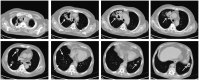

The relationship between antineutrophil cytoplasmic antibody (ANCA)-associated vasculitis (AAV) and lung cancer remains unclear. A 66-year-old man presented with pulmonary nodules. Histological examination of a specimen from computed tomography-guided percutaneous transthoracic biopsy revealed adenocarcinoma. The patient was treated using cryoablation and systemic chemotherapy. Sixteen months later, the patient presented with fever, nasal inflammation, recurrent lung lesions, elevated serum creatinine levels, and high levels of ANCA. Histological examination of a specimen from ultrasound-guided percutaneous renal biopsy revealed pauci-immune necrotizing crescentic glomerulonephritis. The patient responded to treatment, but granulomatosis with polyangiitis recurred and he later died. This case highlights the possibility of sequential AAV with lung cancer. Although this is relatively rare, further research is needed to better understand the association or pathophysiological link between lung cancer and AAV.